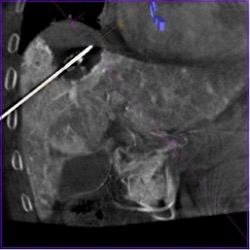

Рис. 13а. Криоабляция метастаза колоректального рака в лёгком (этап визуализации ледяного шара после первого цикла замораживания опухоли с использованием двух криозондов)

Рис. 13б. Криоабляция опухоли малого таза (этап визуализации ледяного шара после второго цикла замораживания опухоли с использованием трех криозондов)

Рис. 13в. Микроволновая абляция узла гепатоцеллюлярного рака стадии BCLC A сразу после выполнения его суперселективной трансартериальной химиоэмболизации (этап визуализации зоны абляции, содержащей «призрак опухоли» сразу после окончания подачи энергии)

Рис. 13г. Стереотаксическая биопсия опухоли головного мозга под ПДКТ-контролем (этап контроля положения биопсийной иглы в опухоли с использованием объединенных (совмещенных) данных: ПДКТ для визуализации иглы и МРТ для визуализации опухоли)

Технологии слияния изображений, использующиеся сегодня в интервенционной радиологии целесообразно разделять на три большие группы. Первая подразумевает слияние определенного массива данных, полученного с использованием ПДКТ с массивом данных от «диагностических модальностей», для которых предполагается большая диагностическая ценность в связи преимуществами того или иного метода исследования (например, слияние ПДКТ/ПЭТ-КТ для взятия биопсии из метаболически активной части опухоли легкого). Для этого осуществляют объединение ПДКТ-массива данных с массивом данных диагностической МСКТ, МРТ или ПЭТ-КТ формате DICOM, а совмещенную информацию (например, о размерах и положении метастаза в печени) накладывают на рентгеноскопию в режиме реального времени с целью проведения таргетирования опухоли во время абляции или взятия биопсии [13, 64]. Основным недостатком такого слияния является то, что информация от разных модальностей, как правило, получается в разные фазы задержки дыхания или положения тела пациента, что делает проведение точного слияния технически очень сложным либо вообще неосуществимым. В будущем эти проблемы возможно будут решены с использованием ИИ-программ, которые в настоящее время еще не дошли до стадии коммерческой реализации. Вторым недостатком слияния «разных модальностей» является «устаревание» информации, полученной на диагностическом этапе. Так, даже при слиянии данных МРТ или МСКТ с данными ПДКТ, несущими информацию о размере и положении опухолей головного мозга (положение и размеры интракраниальных образований не зависят от дыхания и движения тела пациента) перед проведением стереотаксической биопсии, данные, полученные на диагностическом этапе, часто расходятся с данными интрапроцедурной ПДКТ-визуализации, так как глиобластомы могут значительно увеличиваться, а лимфомы наоборот уменьшаться в объеме (на фоне проведения гормонотерапии) за короткий промежуток времени [65]. Таким образом, использование мультимодального слияния изображений (ПДКТ/МСКТ, ПДКТ/МРТ и др.) в настоящее время может быть эффективным при осуществлении вмешательств только на малоподвижных органах (например, на позвоночнике) и только при медленно прогрессирующих заболеваниях (например, во время установки стент-графта в аорту для лечения аневризмы). Поэтому расширение возможностей интраоперационной ПДКТ-визуализации с использованием наиболее эффективных режимов контрастирования является краеугольным камнем повышения дальнейшей точности и безопасности проведения многих рентгенохирургических вмешательств, в том числе ПДКТ-контролируемой стереотаксической биопсии опухолей головного мозга [65].

Более надежным является использование интраоперационного слияния ПДКТ/ПДКТ массивов данных во время ряда интервенционно-радиологических процедур. В качестве примера можно привести возможность слияния данных ПДКТ-артериогепатикографии, несущей информацию о положении и размерах метастаза в печени с данными ПДКТ-артериогепатикографии после выполнения чрескожной энергетической абляции для получения информации о «крае абляции» (по аналогии с краем резекции) с целью оценки технической эффективности проведенного лечения [14, 24].